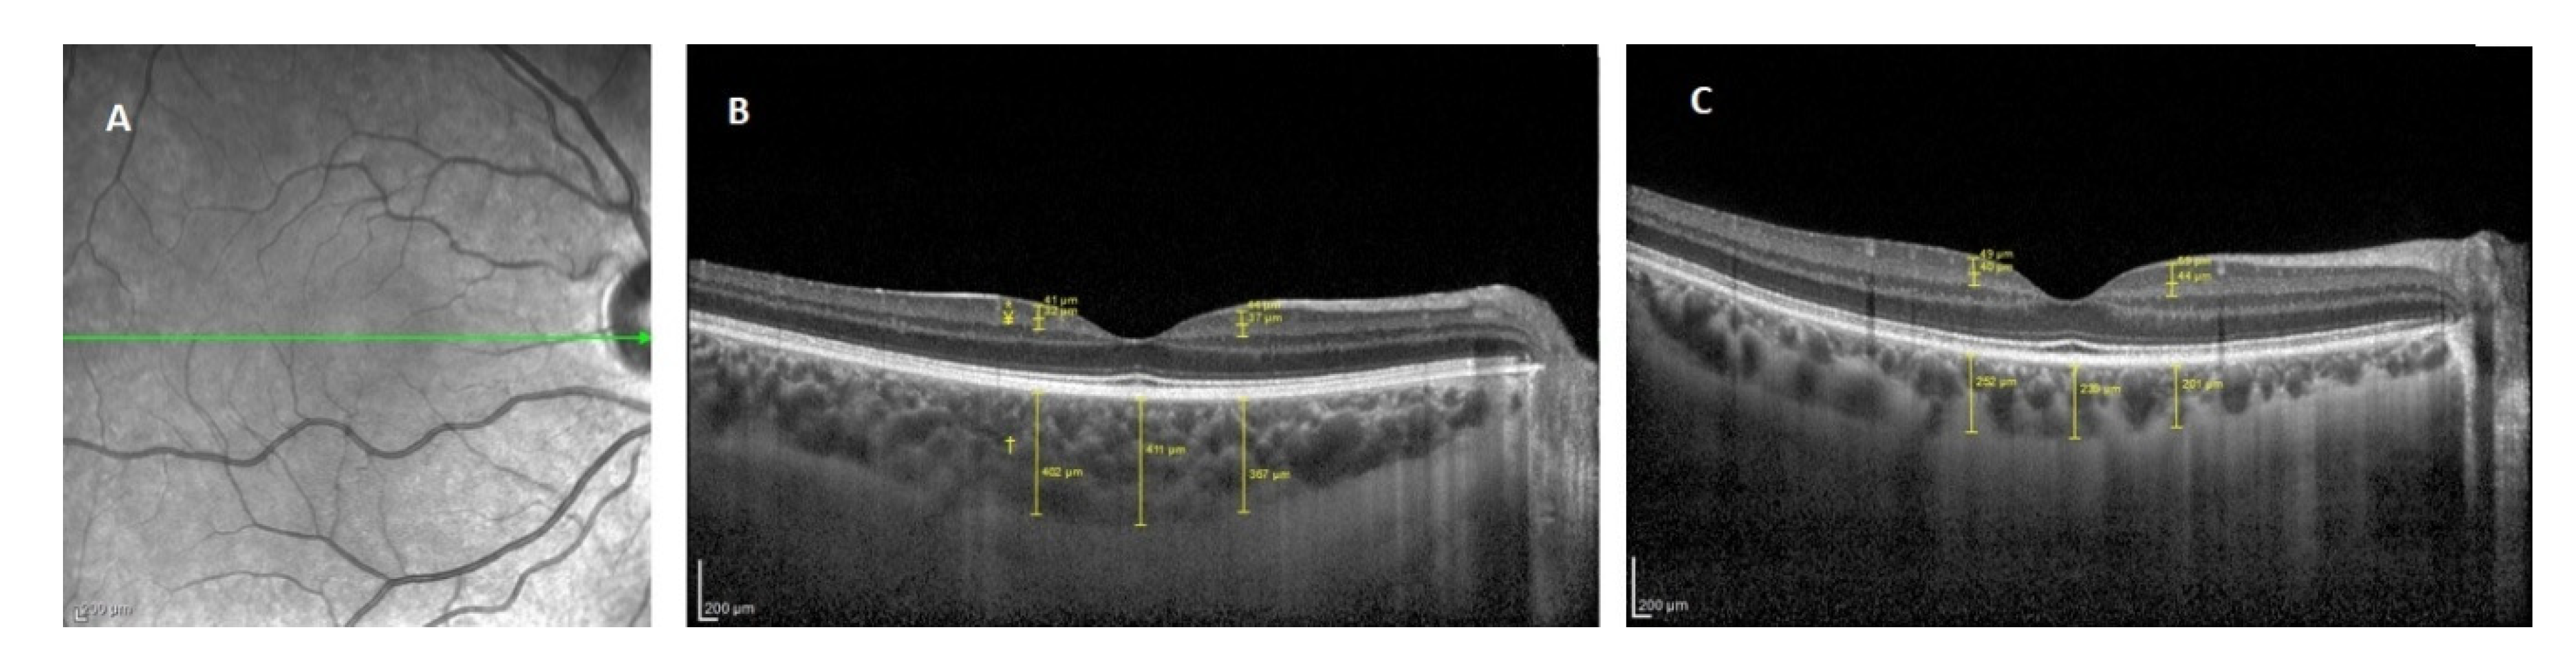

2.2. Clinical Measurments